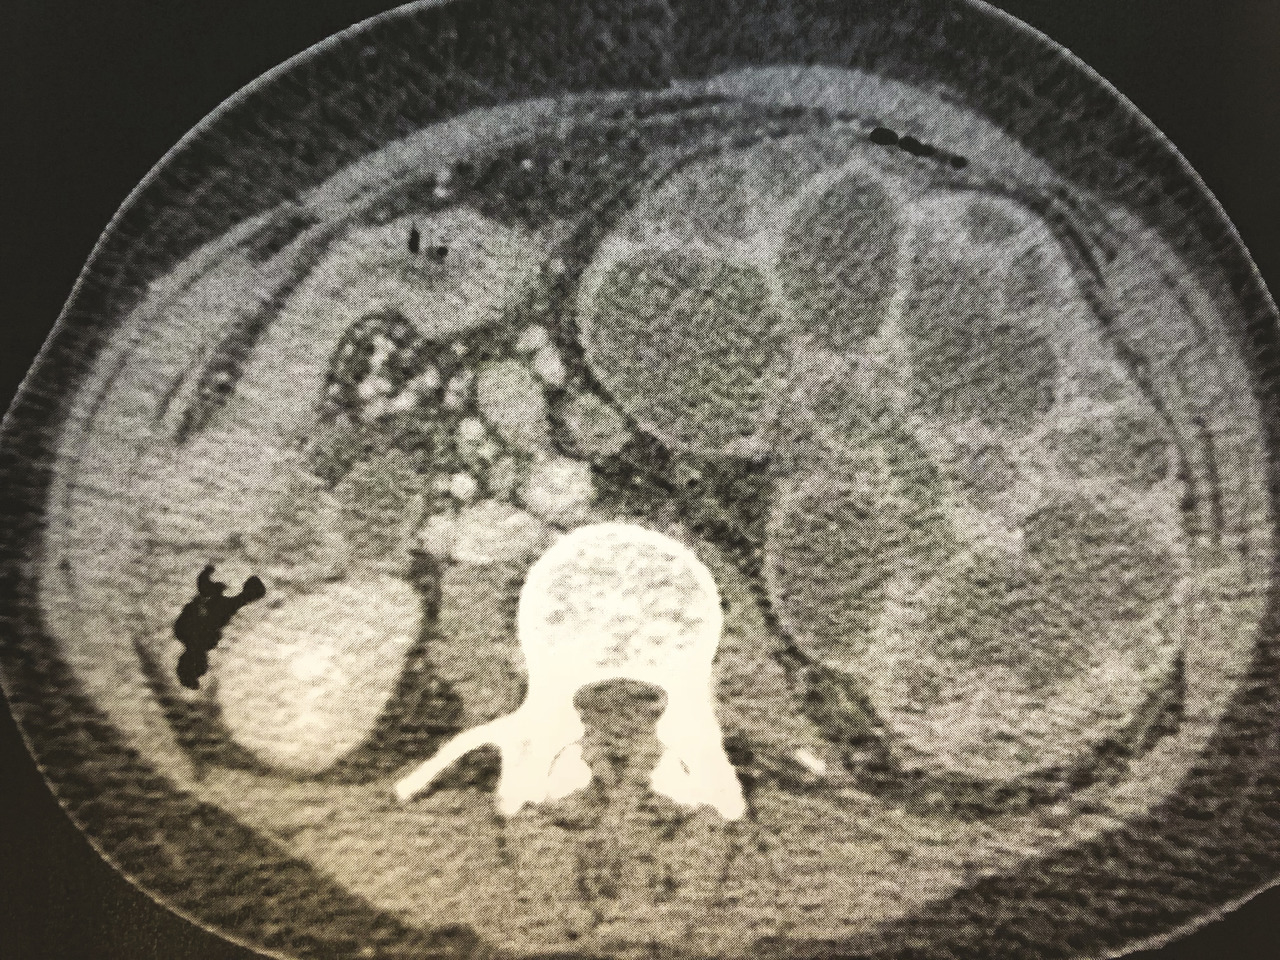

Cette patiente de 33 ans consultait pour des douleurs abdominales fébriles (38,9 °C). L’examen clinique notait une défense du flanc gauche sans autres anomalies. Le bilan biologique montrait des leucocytes à 21 740 /mm3 et une CRP à 312 mg/L. La tomodensitométrie (TDM) abdominopelvienne montrait une hypertrophie rénale gauche de 20 cm de grand axe et une dilatation des cavités pyélocalicielles avec de multiples abcès et cavités liquidiennes en faveur d’une pyélonéphrite xanthogranulomateuse diffuse (fig. 1 et 2). Une antibiothérapie par ceftriaxone, métronidazole et gentamycine était instaurée puis adaptée à l’antibiogramme (Proteus mirabilis multisensible) par amoxicilline seule. En l’absence d’amélioration biologique et à la TDM au 5e jour, une néphrectomie gauche était réalisée (fig. 3). L’anatomopathologie notait un tissu de granulation riche en cellules xanthomateuses et un infiltrat inflammatoire polymorphe remplaçant le parenchyme rénal.

La pyélonéphrite xanthogranulomateuse est une forme rare de pyélonéphrite (0,6 à 1,4 %) touchant surtout les femmes (3/1) entre 50 et 70 ans.1 Sa définition est histologique. Il existe une forme focale avec un tableau clinique pauvre, et une forme diffuse correspondant à une pyonéphrose. La TDM est l’examen de référence : elle permet de chercher un obstacle des voies urinaires et la destruction focale ou complète du rein. Le traitement repose sur une néphrectomie partielle ou totale, associée à une montée de sonde en cas d’obstacle, qui doit être réalisée sous couvert d’une antibiothérapie. Dans la forme focale, quelques cas de guérison par traitement médical seul ont été rapportés.2